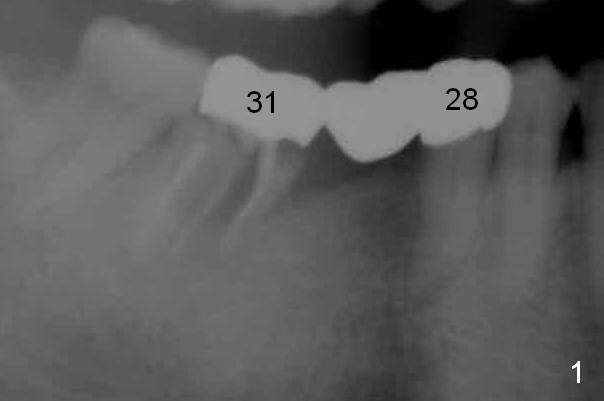

Chief complaint of a 69-year-old lady is "I cannot eat after bottom right bridge removal" (Fig.1). Exam reveals that the tooth #15 is also missing (Fig.2). Four implants are planned. CBCT shows low density of #31 socket (Fig.3,4, bone expanders) and the buccal coronal portion of the #29 socket (Fig.3,6,7, place implant as lingual as possible). The alveolus at the site of #30 is atrophic coronally (Fig.5). If insertion torque of individual implants is reasonably high, an immediate provisional bridge will be fabricated.